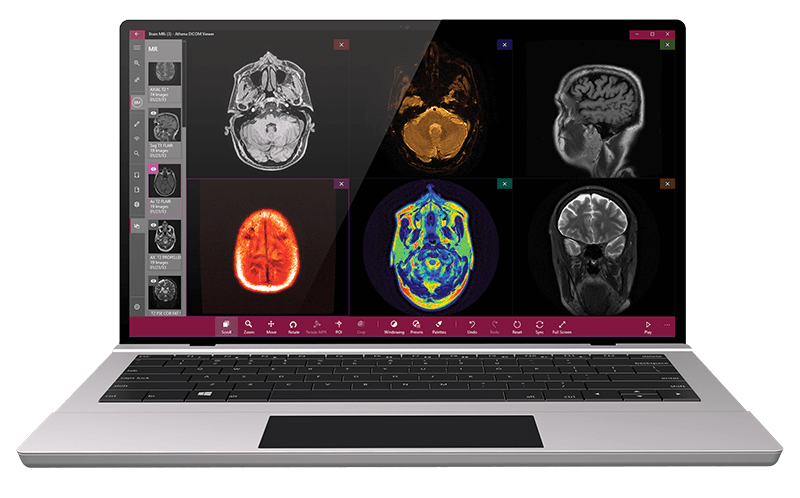

It is a powerful and fast DICOM viewer that is packed with many features. It enables reconstruction, volume rendering and image manipulation by offering several tools to carry out these functions. One unique spec of this application is its voice recognition technology, which helps users when viewing and retrieving files. Voice recognition also enables easy preparation of reports from the DICOM files. The viewer works better on systems with a touchscreen. The free version is only for a trial and purchase is required to access all features.

| 15. | Athena | Windows 10 | Available but in paid version | Y | Y | Y | Y | 500 MB | Intel core/ 8 GB RAM, DirectX Version 10 | Free only for one month |